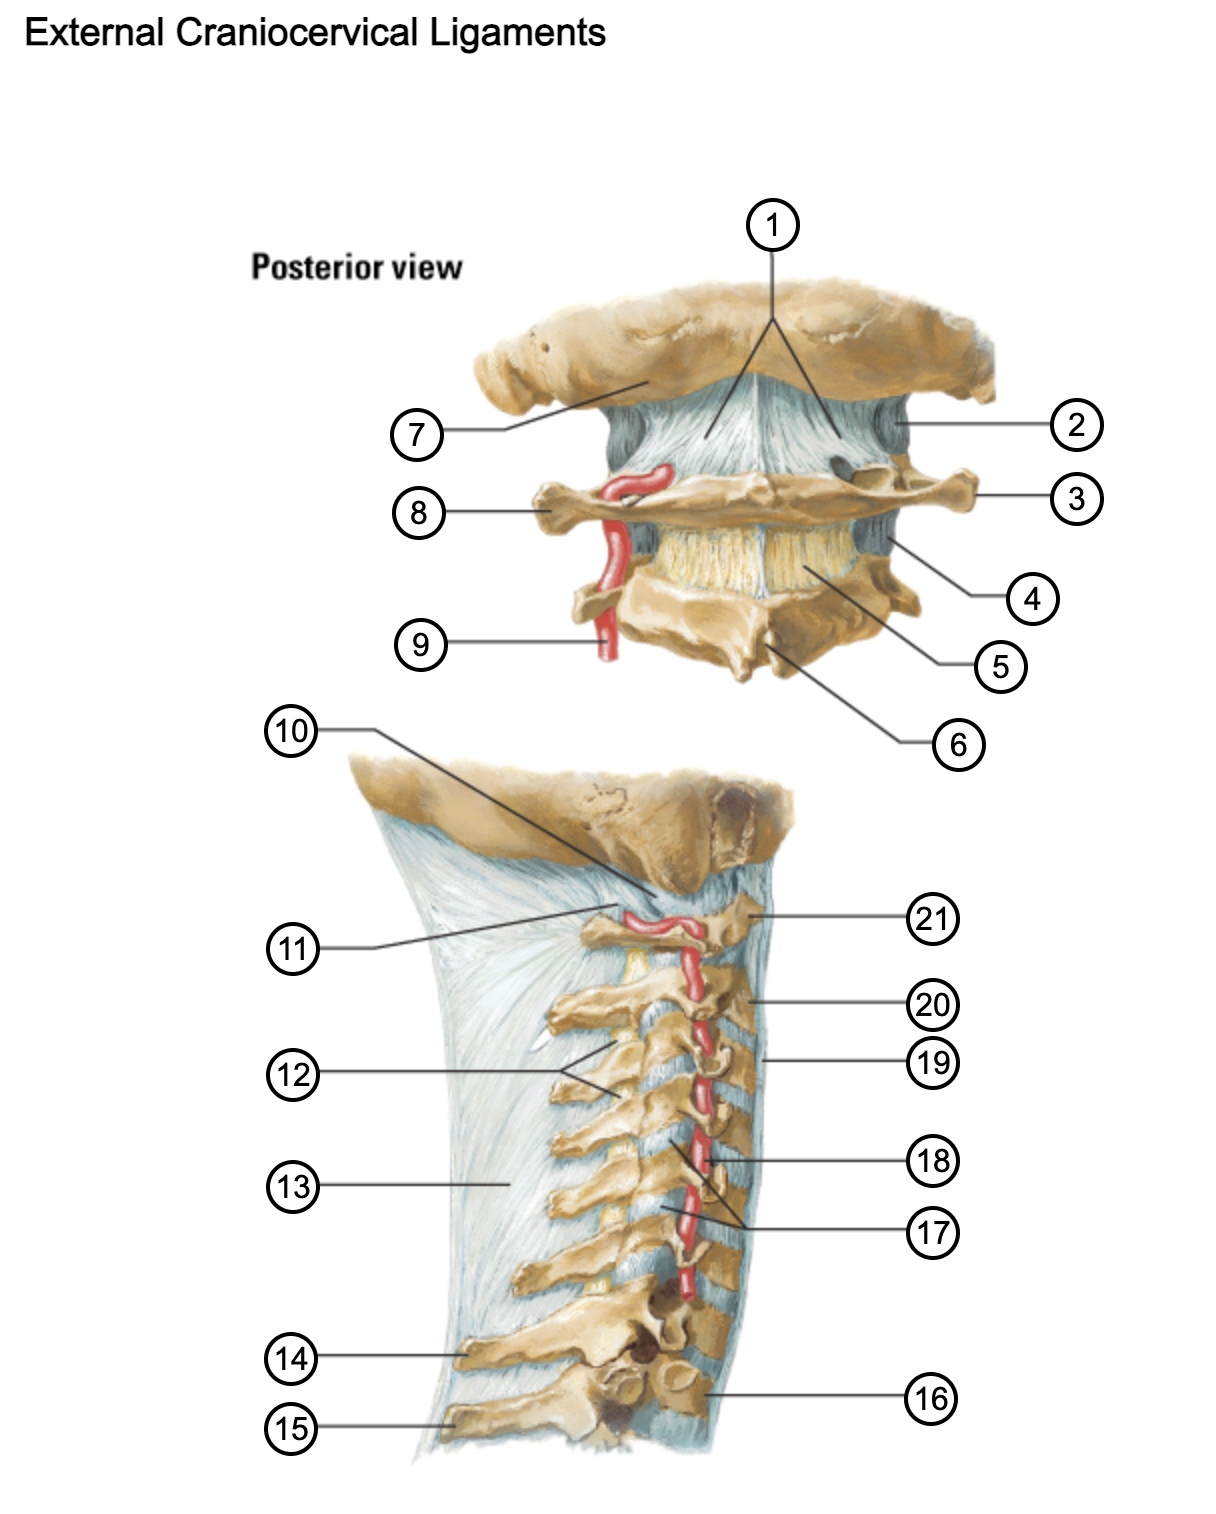

1

posterior antlantooccipital membrane

2

capsule of atlantooccipital joint

3

transverse process of atlas (C1)

4

capsule of lateral atlantoaxial joint

5

ligamenta flava

6

spinous process

7

occipital bone

8

transverse process of atlas (C1)

9

vertebral artery

10

capsule of atlantooccipital membrane

11

posterior atlantooccipital membrane

12

ligamenta flava

13

nuchal ligament

14

spinous process of C7 vertebra

15

spinous process of T1 vertebra

16

T1 vertebra

17

zygapophysical joints (C4-5 and C5-6)

18

vertebral artery

19

anterior longitudinal ligament

20

body of axis

21

Atlas (C1)